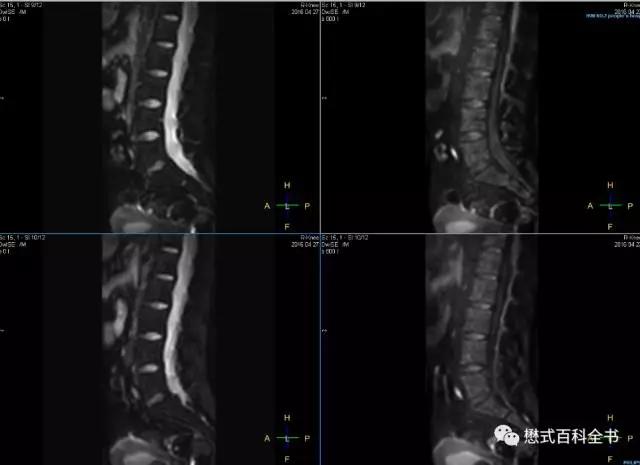

另外,也有医院常规做脊柱DWI扫描的,采用矢状位。推荐B值为500-800这个范围,这样能够权衡信噪比和敏感度。

图16:笔者扫描的一例,腰椎DWI,从左到右,B值分别为0,800。矢状位采集,图像变形小。在3.0T,飞利浦Ingenia上面做的。